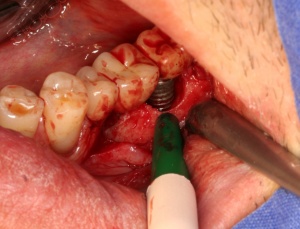

Die Entscheidung für eine regenerative oder eine resektive Therapie (Modul D des Berner Modells) richtet sich nach der knöchernen Defektkonfiguration. Schwarz und Becker (2007) unterschieden in: I. eine horizontale Knochenresorption, II. eine schüsselförmige Knochenresorption, III. eine trichterförmige Knochenresorption und IV. eine spaltförmige Knochenresorption. Wie in der Parodontalchirurgie sollte – soweit vorhanden – mikrochirurgischem Instrumentarium der Vorzug gegeben werden. Die engen periimplantären Verhältnisse bei aufgesetzter Implantatprothetik machen dies notwendig. Der primäre Wundverschluss sollte mit Nahtmaterial 5-0 bis 7-0 erfolgen (Abb. 12, 13, 14, 15, 16).